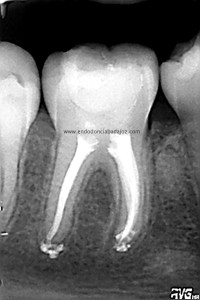

Una vez que hemos limpiado los conductos con un sistema de instrumentación  Protaper en combinación con limas K3. Pasamos a obturar los mismos con una técnica de condensación vertical de ola contínua de Buchanan y un backfilling con la gutapercha inyectada de la pistola ObturaII. Tomamos varias proyecciones, orto-mesio-distal

Con estas tres proyecciones nos quedamos mucho más tranquilos y seguros de un buen sellado hermético y tridimensional des sistema de conductos de esta pieza.